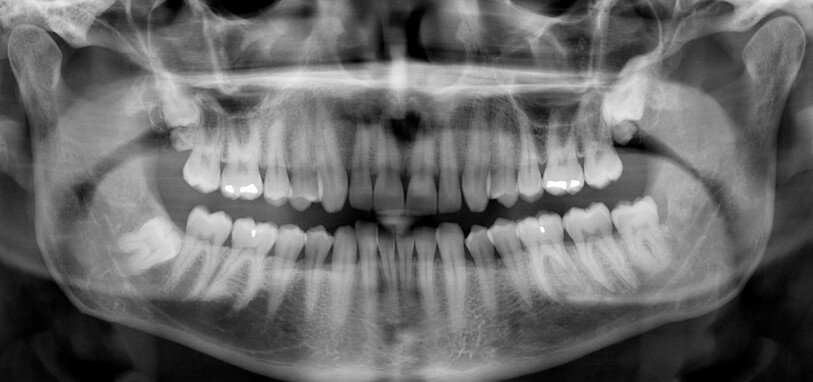

ΟΠΙΣΘΟΦΑΤΝΙΑΚΗ ΑΚΤΙΝΟΓΡΑΦΙΑ

Η οπισθοφατνιακή ακτινογραφία λαμβάνεται με την τοποθέτηση του ακτινογραφικού πλακιδίου εσωτερικά των δοντιών (προς την πλευρά της γλώσσας ή του ουρανίσκου) και παράλληλα με αυτά. Με αυτή απεικονίζονται ένα ή περισσότερα δόντια (τόσο η μύλη, όσο και η ρίζα αυτών), καθώς και τμήμα του φατνιακού οστού που περιβάλλει τις ρίζες των δοντιών. Αποτελεί την πιο απλή οδοντιατρική ακτινογραφική απεικόνιση. Η λήψη της είναι γρήγορη (διαρκεί λίγα δευτερόλεπτα) και ανώδυνη.

Η οπισθοφατνιακή ακτινογραφία μεταξύ άλλων μας επιτρέπει:

- την ανίχνευση οδοντικών τερηδόνων, τον καθορισμό της έκτασης και του βάθους τους και της σχέσης τους με τον πολφό του δοντιού

- τη μελέτη των ριζών των δοντιών (αριθμός, μορφολογία και πιθανή κάμψη αυτών, ύπαρξη απορρόφησης ή κατάγματος)

- τη μελέτη του αριθμού, της μορφολογίας, του εύρους και της πορείας των ριζικών σωλήνων εντός των ριζών

- τη μελέτη των σκληρών ιστών του περιοδοντίου, δηλαδή του φατνιακού οστού που περιβάλλει και στηρίζει το δόντι και του περιοδοντικού συνδέσμου. Σε περίπτωση περιοδοντικής νόσου, καθορίζεται η εντόπιση, ο βαθμός και η φύση (οριζόντια, γωνιώδης) της απορρόφησης του φατνιακού οστού

- τη μελέτη του φατνιακού οστού της περιακρορριζικής περιοχής του δοντιού για ύπαρξη παθολογικών εξεργασιών (απόστημα, κοκκίωμα, κύστη κ.λ.π.)

- την ανίχνευση κατάγματος των δοντιών.